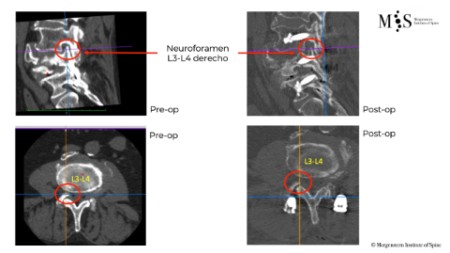

Exemple cas clínic cifoplastia

Comparació pre- i post-operatoria d’una cifopastia cementada

Dona, edat 55 anys, fractura aixafament dret de L2

Abans 1

Després 1

Abans 2

Després 2